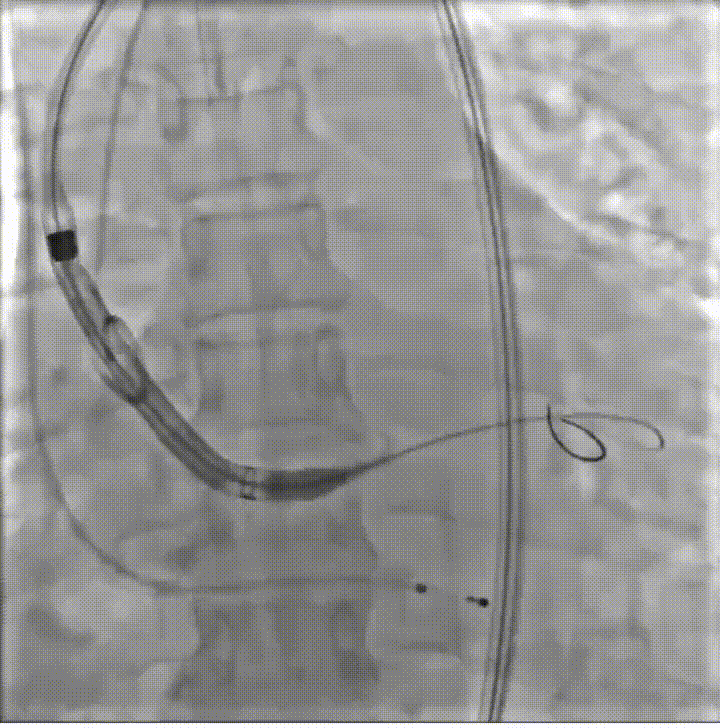

患者病史 体检发现心脏瓣膜病半月余,平素无症状 ,有高血压病史。 后来院复查诊断为:主动脉瓣狭窄(重度)、先天性主动脉瓣二叶瓣畸形、心室肥厚、升主动脉扩张心功能 I 级(NYHA 分级)、高血压病 2 级(极高危)。 术前 CT:Type0型二叶瓣,瓣叶增厚,无钙化,类风湿性;瓣环径25.6mm,LVOT稍收窄,瓣环水平夹角66.6°,轻微横位心;左右冠开口高度可,瓣叶不长,无冠脉风险;心室收缩末内径约32mm,室壁增厚;外周入路无明显迂曲,无钙化、双侧内径可、双股中分叉,右侧为主入路能够支持20F大鞘通过。 造影角度及入路:LAO 6° CAU 13° 手术策略 采用右侧股动脉为主入路,左侧为辅助入路,常规穿刺。推荐使用20球囊预扩,预装TAV29瓣膜,初始定位对齐瓣环上0mm开始释放。 手术过程 20号球囊预扩无明显腰征 输送器过弓跨瓣顺滑 80%工作位观察 术后造影,瓣膜释放位置良好,无瓣周漏 术后超声:人工生物瓣释放后形态满意,瓣叶开放、关闭活动良好,无瓣周漏;跨瓣血流速度降至 2.5m/s,平均压力梯度6mmHg,符合手术预期。 Prostyle A®预装干瓣——“刚柔并济”助力临床最优化解决方案: 丝滑过弓能力:Prostyle A®短瓣架设计联合远端超滑亲水涂层,即使没有联合使用snare,都可以柔顺过弓,该例横位心的患者更好的展现了输送系统的柔顺性; 平衡的径向支撑力:该例患者Type0型二叶瓣,术后形态展开良好且无瓣周漏,在横位心等复杂情况下实现稳定锚定。 80%可回收设计:80%工作位观察,起搏时间更短,对患者损伤减少到最小,也利于术中精准调整瓣膜位置,保证术后效果。